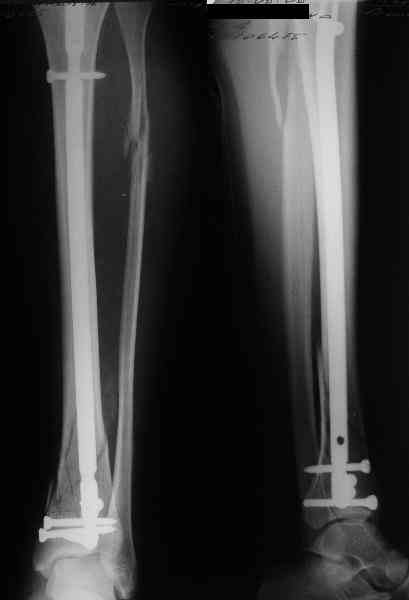

В приложении пример лечения аналогичного повреждения (плюс задний край).